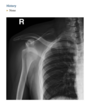

61yr old woman with shoulder pain

AP Radiograph of left shoulder in external and internal rotation (1 & 2) - globular foci of calcification in expected location of supraspinatus (White arrow) and infraspinatus (black arrow) and pectorals major

DIAGNOSIS: Hydroxyapatite deposition disease

(HADD)

HADD consists of crystal deposition in

and around joints, without a known cause.

AKA calcific tendonitis

On radiographs, the calcium deposits appear cloud-

like and amorphous and can involve the tendon,

ligament, bursa, or joint capsule. Intraarticular crys-

tal deposition can destroy the joint space, resulting

in a condition referred to as “Milwaukee shoulder.”

On CT,

­ accompanying erosion of the underlying bone can be

seen. CT appearance has been described as commonly

having a flame-shaped or comet-tail configuration of

the calcifications

If not in shoulder/region not common for HADD ?Malignancy